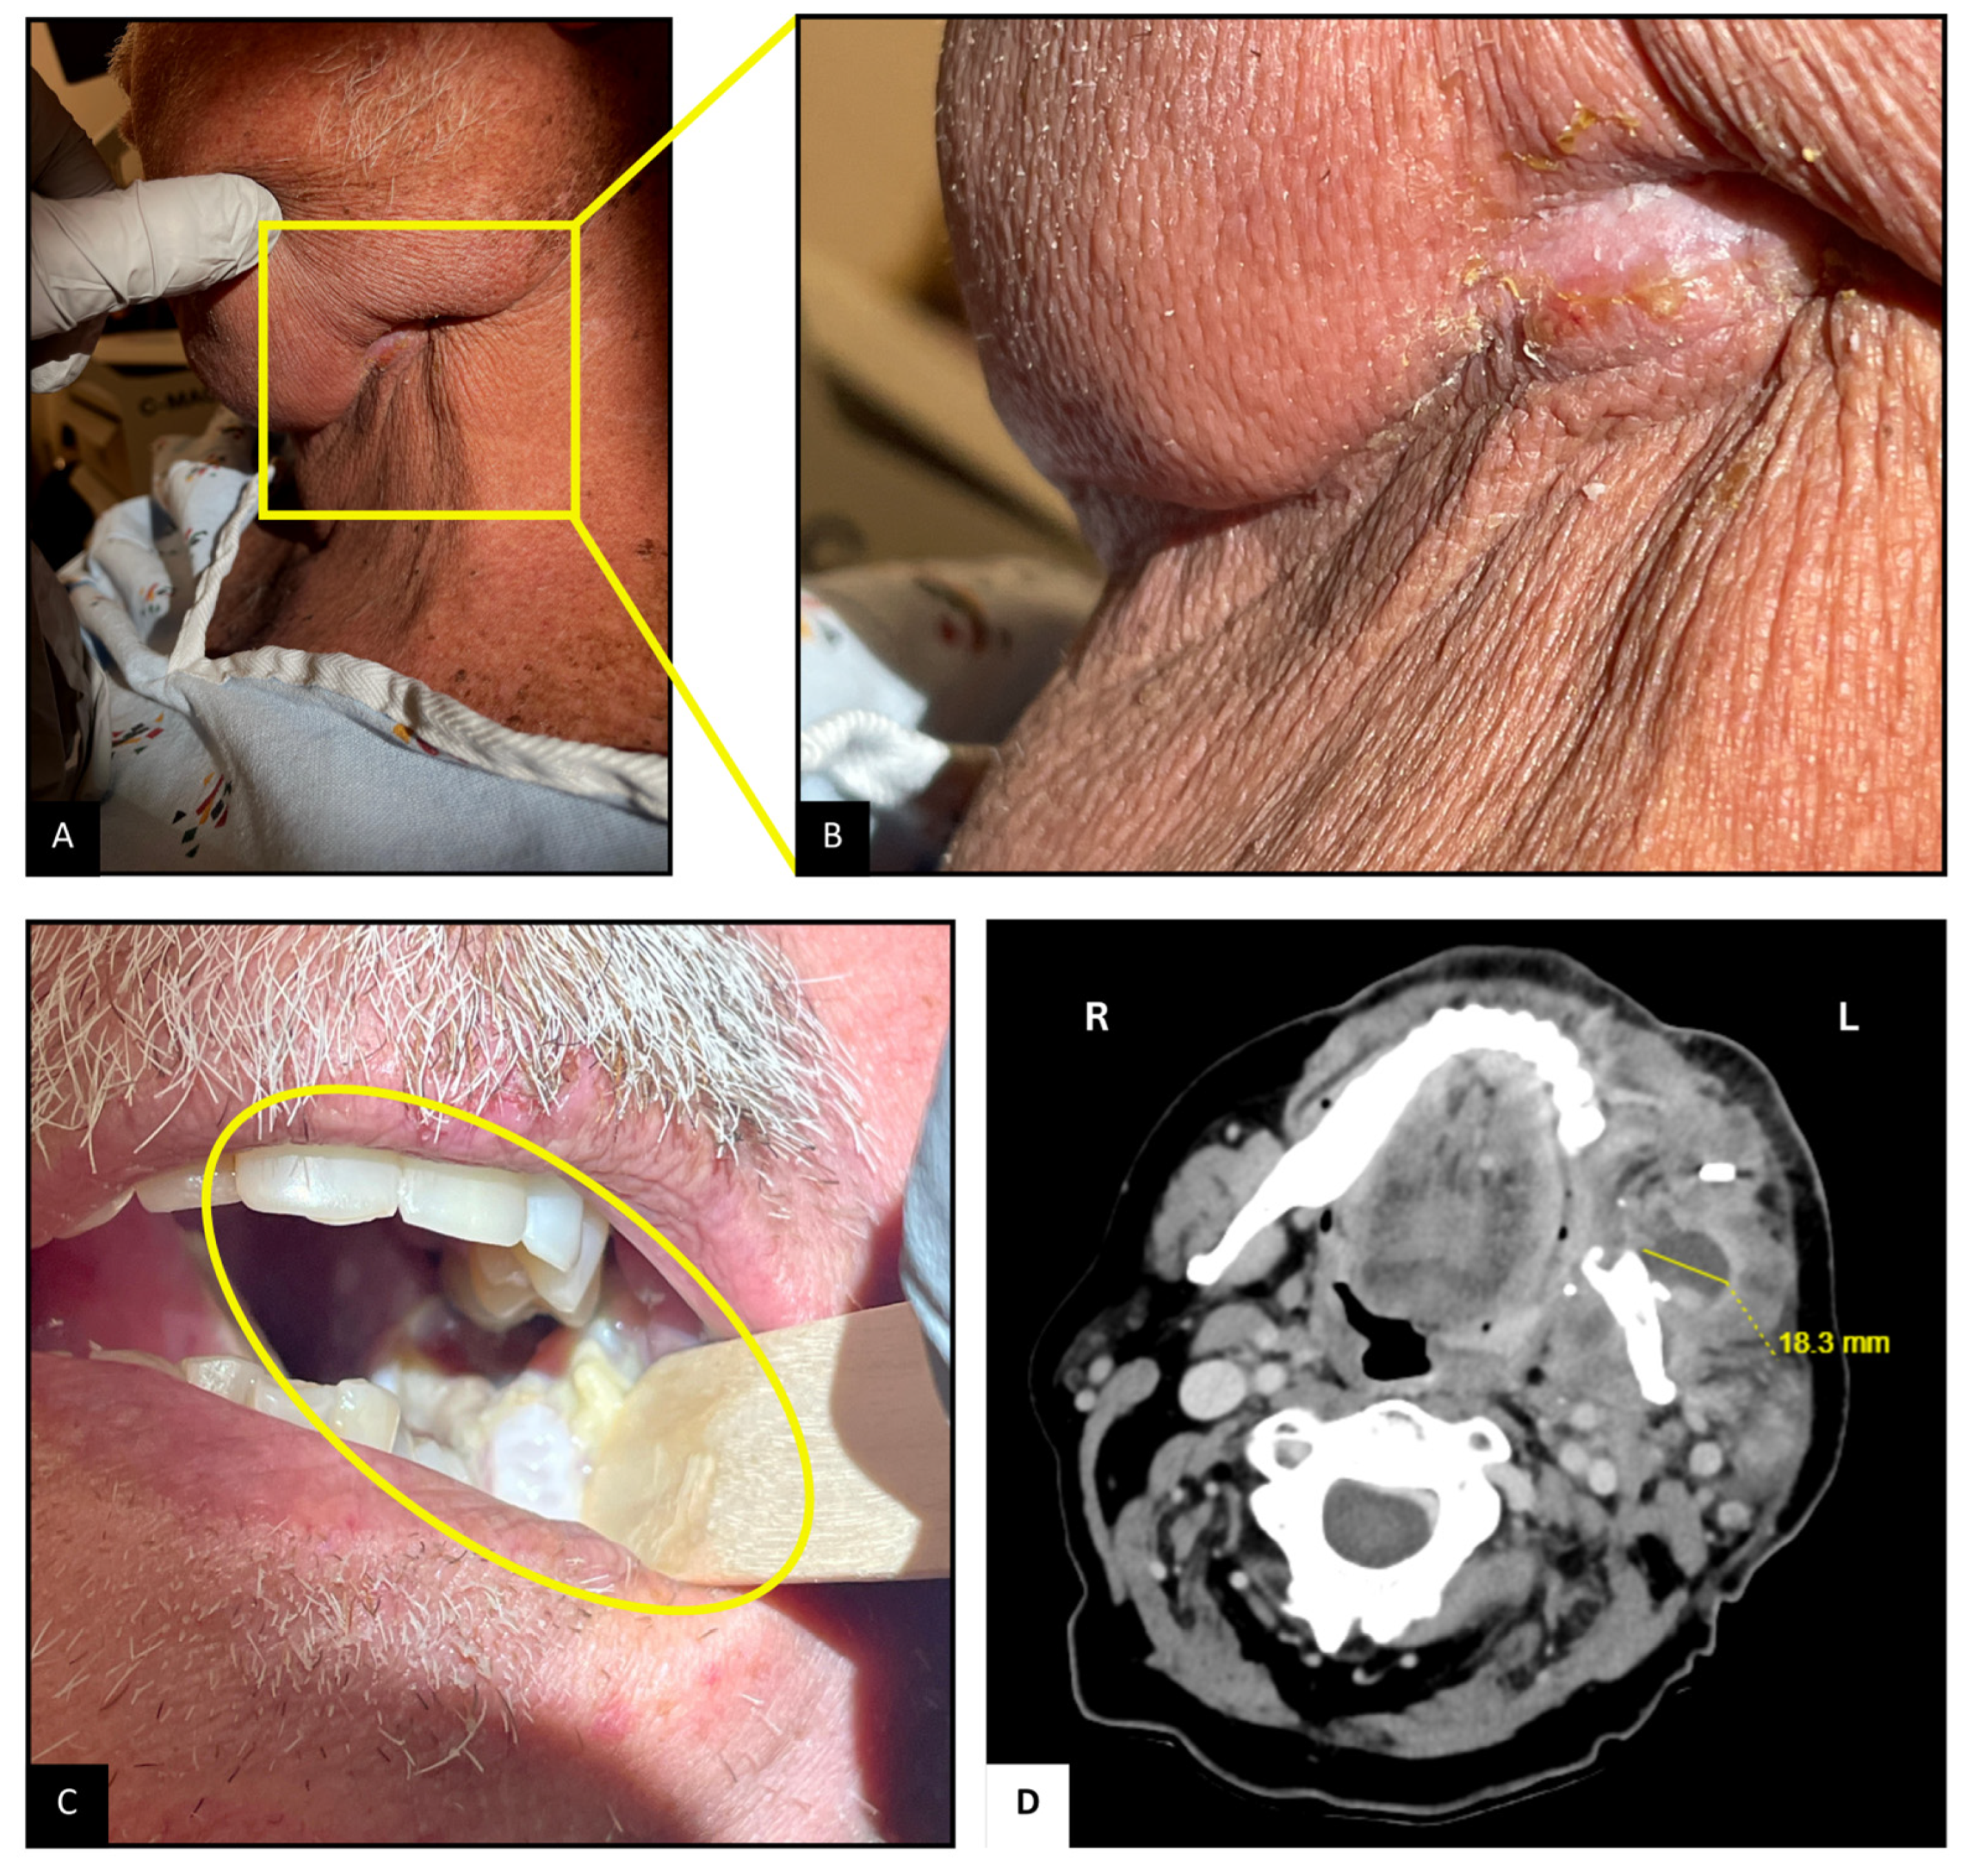

Upon arrival, the patient was hemodynamically stable. Examination revealed mild left facial swelling without any erythema or drainage, but a 1 cm long scabbed incision below the left mandibular angle, possibly the site of lymph node dissection (Figure 1A,B). Tenderness was noted on palpation. Inspection of the oropharyngeal mucosa revealed sloughing at the left retromolar trigone, with part of the flap used for reconstruction caught within the occlusion line (Figure 1C). Erythema suggestive of post-radiation mucositis was also noted around the pharynx. Abdominal examination revealed mild distention and tenderness, particularly in the lower quadrants, likely due to fecal retention from opioid-related constipation. The remainder of the examination was unremarkable.

Figure 1.

Neck and Oropharyngeal Examination and Imaging. (A,B): Scabbed incision below the left mandibular angle. (C): Sloughing and mucositis at the left retromolar trigone; flap caught in occlusion line. (D): CT scan showing 2.3 × 1.8 cm2 complex abscesses at the left retromolar region, with associated mandibular irregularity.

Contrast-enhanced CT (Figure 1D) of the neck revealed a complex abscess 2.3 × 1.8 cm2 at the left retromolar region extending into the masseter muscle, irregularity of the adjacent mandibular surface, and an enlarged left supraclavicular node. Ultrasound-guided aspiration with biopsy of the abscess yielded approximately 3 mL of purulent material. Gram staining was consistent with branching Gram-positive bacilli, and acid-fast staining demonstrated partially acid-fast organisms. Head MRI was suggestive of possible left mandibular angle osteomyelitis and compression of the inferior alveolar nerve, with no acute intracranial abnormalities. Given the positive CT scan, a dedicated neck MRI was deemed unnecessary. A non-contrast CT scan of the chest revealed bilateral ground-glass opacities, likely residual from a previous organizing pneumonia, but no new findings.